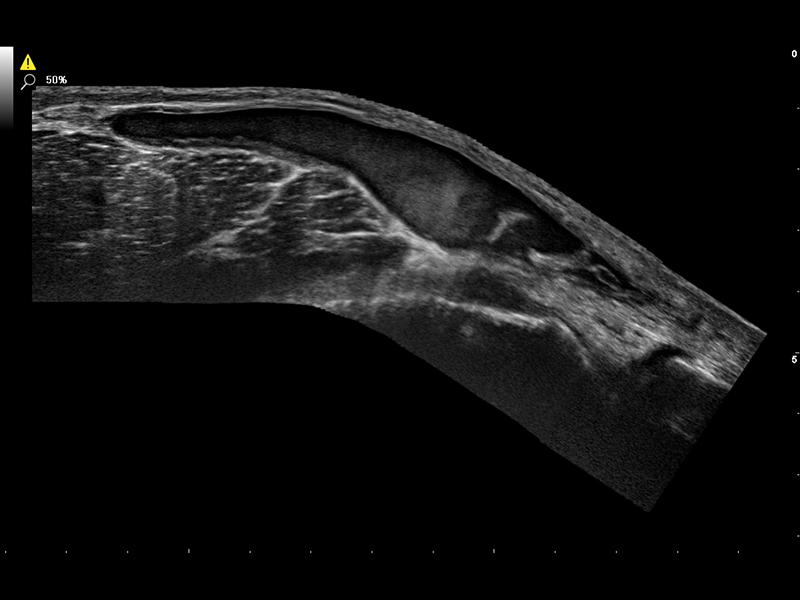

Interventional procedures in musculoskeletal applications are used to diagnose and treat conditions affecting bones, joints, muscles, tendons, ligaments, and other related structures.

These procedures are often performed under ultrasound imaging guidance to increase accuracy and precision, such as in infiltrations where the brightness of the needle can be emphasized by using Esaote’s advanced Needle Enhancement tool. Virtual Navigator (VNav) is the Esaote technology for fusion imaging that enables US examiners to combine real-time ultrasound with datasets from second modalities to increase diagnostic accuracy and provide a more comprehensive understanding of a particular region of interest.

In MSK, fusion imaging between CT/MRI and US can be particularly valuable, for example for joint injections and biopsies.